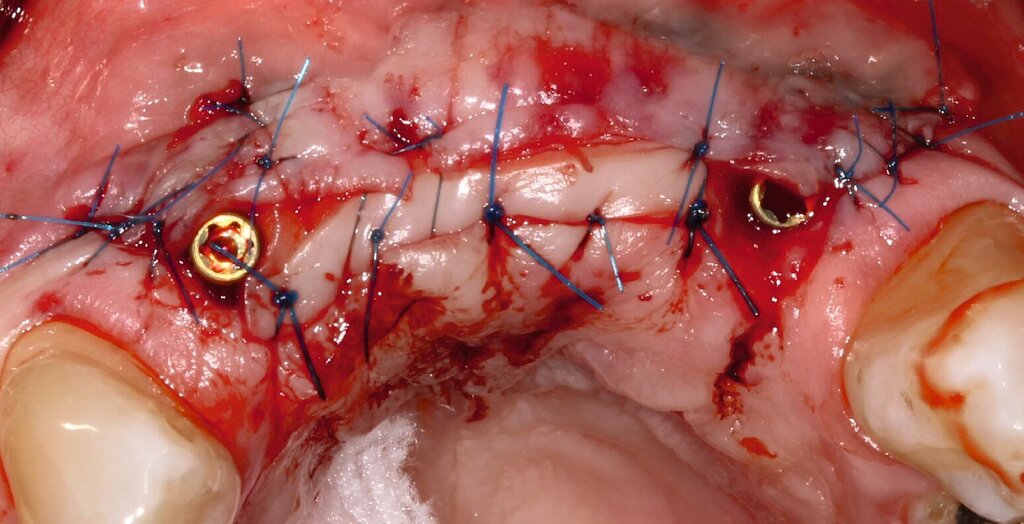

Da sechs Monate nach der Explantation keine nennenswerte knöcherne Regeneration festzustellen war, wurde eine zweizeitige Implantation nach Knochenaugmentation mithilfe dünner Knochenscheiben aus dem Kieferwinkel geplant. Die Entnahme erfolgte mit oszillierenden Instrumenten (Piezosurgery). Der Knochenblock wurde in dünne Scheiben geschnitten und mit Osteosyntheseschrauben am Alveolarfortsatz fixiert (Abb. 3e). Darüber wurden die Weichgewebe dicht vernäht. Weitere fünf Monate später erfolgte die Schraubenentfernung und die Implantation von zwei Bone-Level-Implantaten in regio 12 und 22 mit geschlossener Einheilung (Abb. 3f und 3g). Bei der Implantatfreilegung weitere sechs Monate später wurden die Weichgewebsdefizite im Brückengliedbereich durch ein kombiniertes Bindegewebs-/Schleimhauttransplantat aufgefüllt und gleichzeitig die keratinisierte periimplantäre Gingiva und Alveloarmukosa verbreitert (Abb. 3h und 3i). Die prothetische Versorgung erfolgte erst weitere drei Monate später, nach dem Konsolidieren der Weichgewebe. Die umfangreichen Augmentationsmaßnahmen konnten das transversale Weichgewebsdefizit vollständig kompensieren, während das verbleibende vertikale Defizit zu zervikal etwas längeren Kronen und Brückengliedern führte. Aufgrund der guten Abdeckung durch die Oberlippe kann das ästhetische Ergebnis als zufriedenstellend bewertet werden (Abb. 3j bis 3l).